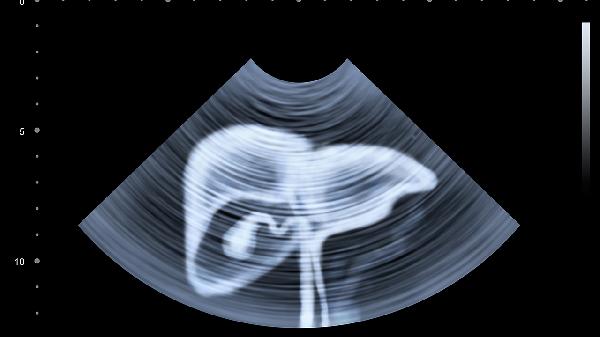

4、肝脾触诊:

肝脏触诊从右髂窝开始,配合呼吸运动,正常肋下≤1cm。脾肿大时向右下腹延伸,需测量甲乙线、甲丙线。肝硬化患者触诊手法需轻柔,避免门静脉高压导致出血。儿童肝脾触诊需考虑年龄标准,新生儿肝脏占腹腔比例较大属正常现象。